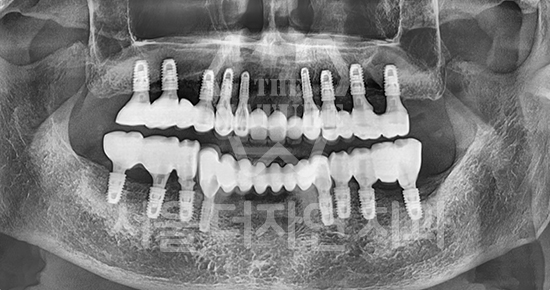

Various Implant Treatment Cases

#Full Mouth Implants

• BEFORE: 2022.12.15

• AFTER: 2023.02.23

#Sinus Lift

• BEFORE: 2021.02.01

• AFTER: 2021.05.13

#Maxillary Bone Grafting

• BEFORE: 2021.11.02

• AFTER: 2022.01.19

Treatment outcomes may vary by patient,

and side effects may occur. These images were taken under the same conditions,

and were published with the patient's consent.